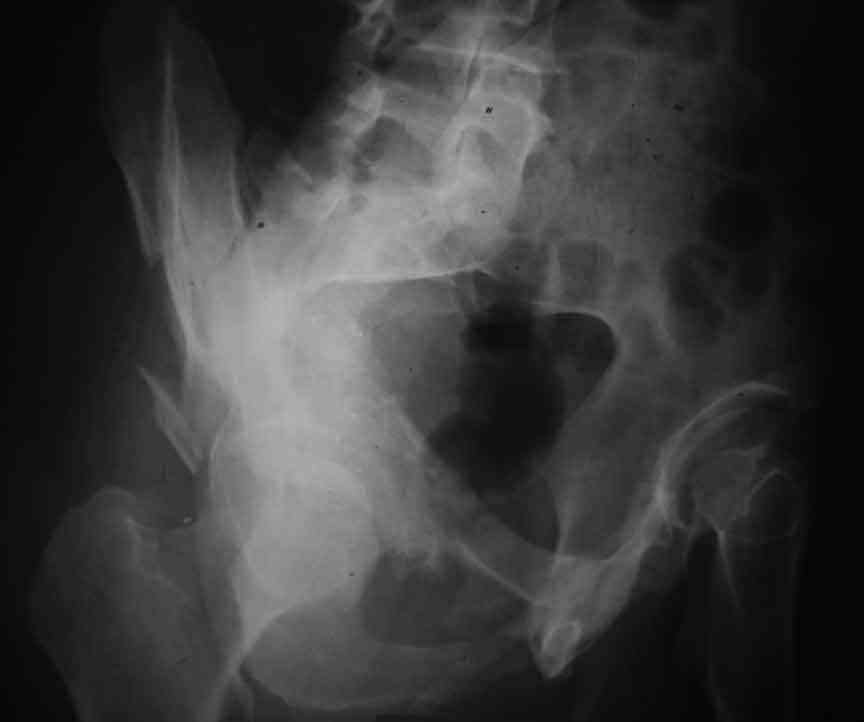

Dear Friends This is a 57 y old male.

Your input is welcome as to the classification of this fratcure, as well as the proposed management.

Dear Sir it looks quite difficult classify this fracture because the iliac view is not so clear.

In my opinion it is a column fracture because the obturator foramen is interrupted. There is a fracture of the posterior wall. If we assume the ap view as an iliac view it could be an anterior comun fracture plus posterior wall. It is difficult also to judge the head of the femur.

From the x rays it appears like a bicolumnar fracture with iliac extension (AO C1).

I am sending another iliac view, and a marked version of the AP I already sent. In this AP, the

proximal part of the greater sciatic notch as well as the distal parts of the ilioischial and iliopubic lines are marked with a grey interrupted line. A white interrupted line marks what could be an exit through the obturator foramen, or so I assume.